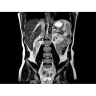

МРТ аппарат GE Optima MR450w 1.5T

МР-томограф с широким туннелем Optima MR450w является настоящей рабочей лошадкой и может эффективно обслуживать большее число пациентов. Томограф обеспечивает одновременно удобство пациента, продуктивность работы, отличное качество изображения. В этой МРТ-системе инженерам компании удалось без компромиссов совместить необходимый объем перемещения с удивительно высоким качеством изображения.